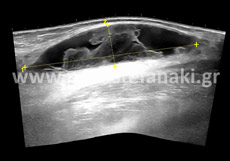

Υπερηχογράφημα Μαστών

Το υπερηχογράφημα μαστών αποτελεί μία από τις εξετάσεις διερεύνησης της παθολογίας του μαστού

Προετοιμασία ασθενούς Δεν απαιτείται.

Πρέπει να προσκομίσετε προηγούμενη μαστογραφία ή/και υπερήχους μαστών.